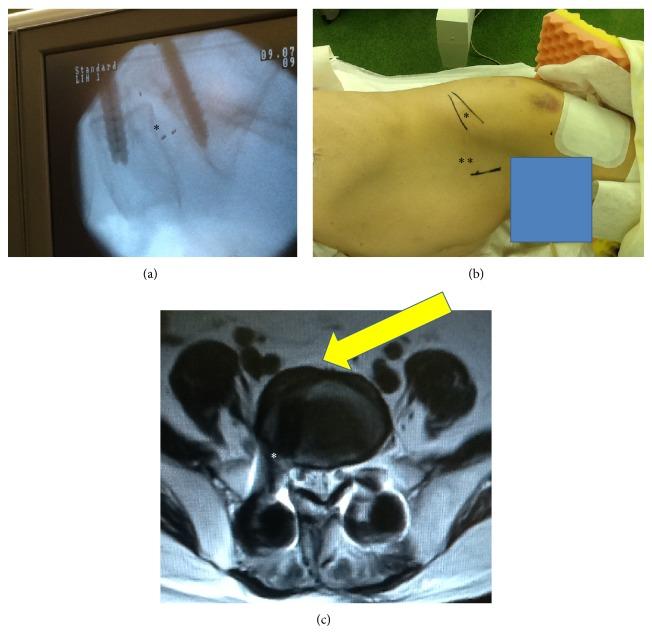

Extreme lateral interbody fusion (XLIF) has been widely used for minimally invasive anterior lumbar interbody fusion (ALIF), but an approach to L5-S1 is difficult because of the iliac crest. In the current study, we present 2 cases using minimally invasive oblique lateral interbody fusion (OLIF) of L5-S1. The patients showed foraminal stenosis between L5 and S1 and severe low back and leg pain. The patients were placed in a lateral decubitus position and underwent OLIF surgery (using a cage and bone graft from the iliac crest) without posterior decompression. Posterior screws were used in the patients. Pain scores significantly improved after surgery. There was no spinal nerve, major vessel, peritoneal, or urinary injury. OLIF surgery was minimally invasive and produced good surgical results without complications.

极外侧椎间融合术(XLIF)已广泛应用于微创前路腰椎椎间融合术(ALIF),但由于髂嵴的存在,L5-S1节段的手术入路较为困难。在本研究中,我们展示了2例采用L5-S1微创斜外侧椎间融合术(OLIF)的病例。患者表现为L5和S1之间的椎间孔狭窄以及严重的腰腿痛。患者取侧卧位,接受OLIF手术(使用椎间融合器和取自髂嵴的骨移植),未进行后路减压。患者使用了后路螺钉。术后疼痛评分显著改善。未发生脊神经、大血管、腹膜或泌尿系统损伤。OLIF手术具有微创性,手术效果良好,无并发症发生。